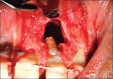

Palatogingival groove is an anatomical malformation that often causes severe periodontal defects. Treatments of such an anomaly present a clinical challenge to the operator. Careful endodontic and periodontal procedures may restore the form and function. In the present case; root canal therapy, apicectomy, and sealing of the groove with Biodentine™ were done. Bone graft was placed followed by platelet-rich fibrin (PRF) membrane. This treatment modality resulted in gain in attachment, reduction in pocket depth, and deposition of bone in the osseous defect. A 24 month follow-up is included.